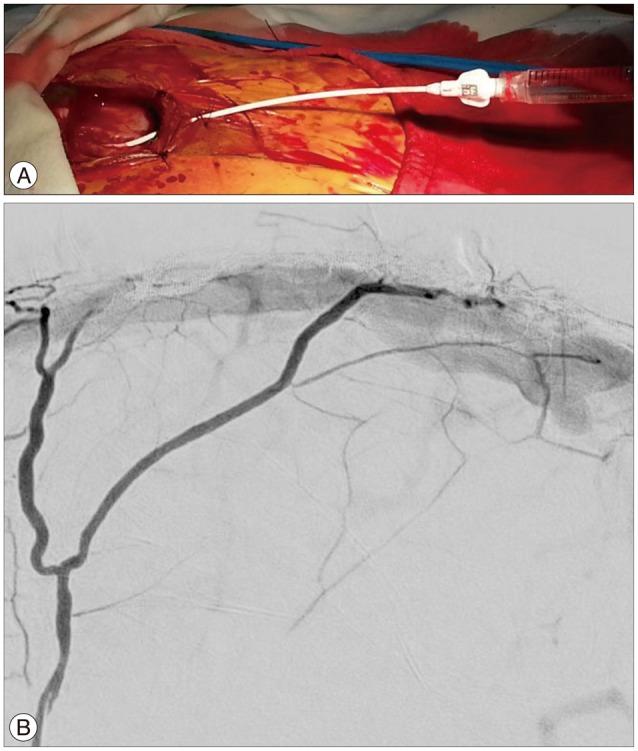

A 66-year-old woman presented with intermittent paraparesis and generalized tonic-clonic seizure. Cerebral angiography demonstrated dural arteriovenous fistula (AVF) involving superior sagittal sinus (SSS), which was associated with SSS occlusion on the posterior one third. The dural AVF was fed by bilateral middle meningeal arteries (MMAs), superficial temporal arteries (STAs) and occipital arteries with marked retrograde cortical venous reflux. Transfemoral arterial Onyx embolization was performed through right MMA and STA, but it was not successful, which resulted in partial obliteration of dural AVF because of tortuous MMA preventing the microcatheter from reaching the fistula closely enough. Second procedure was performed through left MMA accessed by direct MMA puncture following small decortications of cranium overlying the MMA using diamond drill one week later. Microcatheter could be located far distally to the fistula through 5 F sheath placed into the MMA and complete obliteration of dural AVF was achieved using 3.9 cc of Onyx.

一名66岁女性出现间歇性双下肢轻瘫和全身性强直阵挛发作。脑血管造影显示硬脑膜动静脉瘘(AVF)累及上矢状窦(SSS),且与后三分之一的上矢状窦闭塞有关。该硬脑膜AVF由双侧脑膜中动脉(MMA)、颞浅动脉(STA)和枕动脉供血,伴有明显的皮质静脉逆行回流。通过右侧MMA和STA进行了经股动脉Onyx栓塞,但未成功,由于MMA迂曲,微导管无法足够接近瘘口,导致硬脑膜AVF部分闭塞。一周后,使用金刚石钻头在覆盖MMA的颅骨上进行小范围去骨皮质后,通过直接穿刺MMA进入左侧MMA进行了第二次手术。通过置于MMA的5F鞘管,微导管能够置于瘘口远端,使用3.9 cc Onyx实现了硬脑膜AVF的完全闭塞。